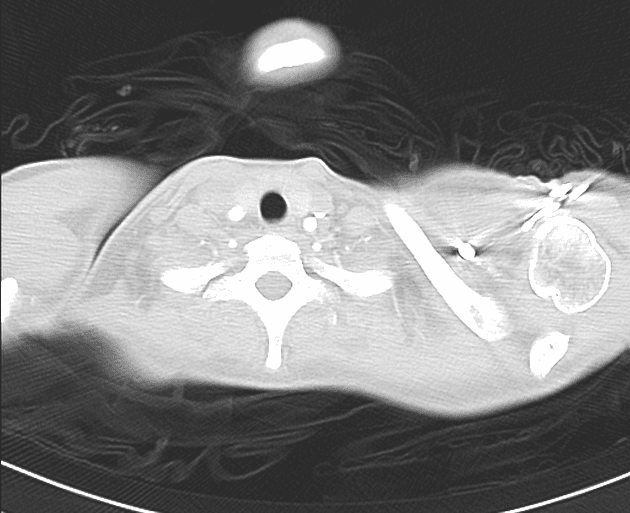

- Tổn thương xâm nhập chủ yếu ở thuỳ trên bên phải.

- Các ổ khí trong tổn thương đặc trưng, không có mức dịch.

- Dấu hiệu vòng ngược (reverse halo) hay còn gọi là dấu hiệu đảo san hô (atoll sign).

- "Dấu hiệu vòng ngược (dấu hiệu đảo san hô) là một hình ảnh CT đặc trưng gồm vùng mờ kính mờ trung tâm được bao quanh bởi vành đặc chắc hình lưỡi liềm hoặc hình vòng, thường gặp trong các nhiễm trùng nấm xâm lấn ở bệnh nhân suy giảm miễn dịch."